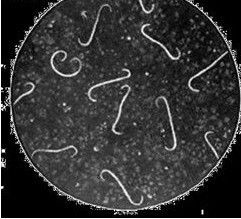

據新華社上海4月24日電(記者葉國標)國家人類基因組南方研究中心執行主任趙國屏教授24日在滬宣布,一個以中國科學家為主、有法國與美國科學家參與的研究團隊,經過3年努力,完成了鉤端螺旋體病的致病菌———問號鉤端螺旋體的全基因組測序及注釋,有關成果24日在國際權威科學雜誌《自然》上發布。

由問號鉤端螺旋體引起的鉤端螺旋體病,是威脅人類健康和畜牧業生產的常見的人獸共患病之一,分布在世界各地,特別是在以水稻種植為主的第三世界國家和地區較為多見。洪水等自然災害常可促發此病的暴發流行,它是歷史上一些大水之後“大疫”的主要疫病之一。由於人們對其致病和免疫機制了解粗淺,至今缺乏簡便的診斷手段和高效安全的疫苗,雖然抗生素治療有一定效果,但它依然是一種潛在的危害嚴重的自然疫源性疾病。